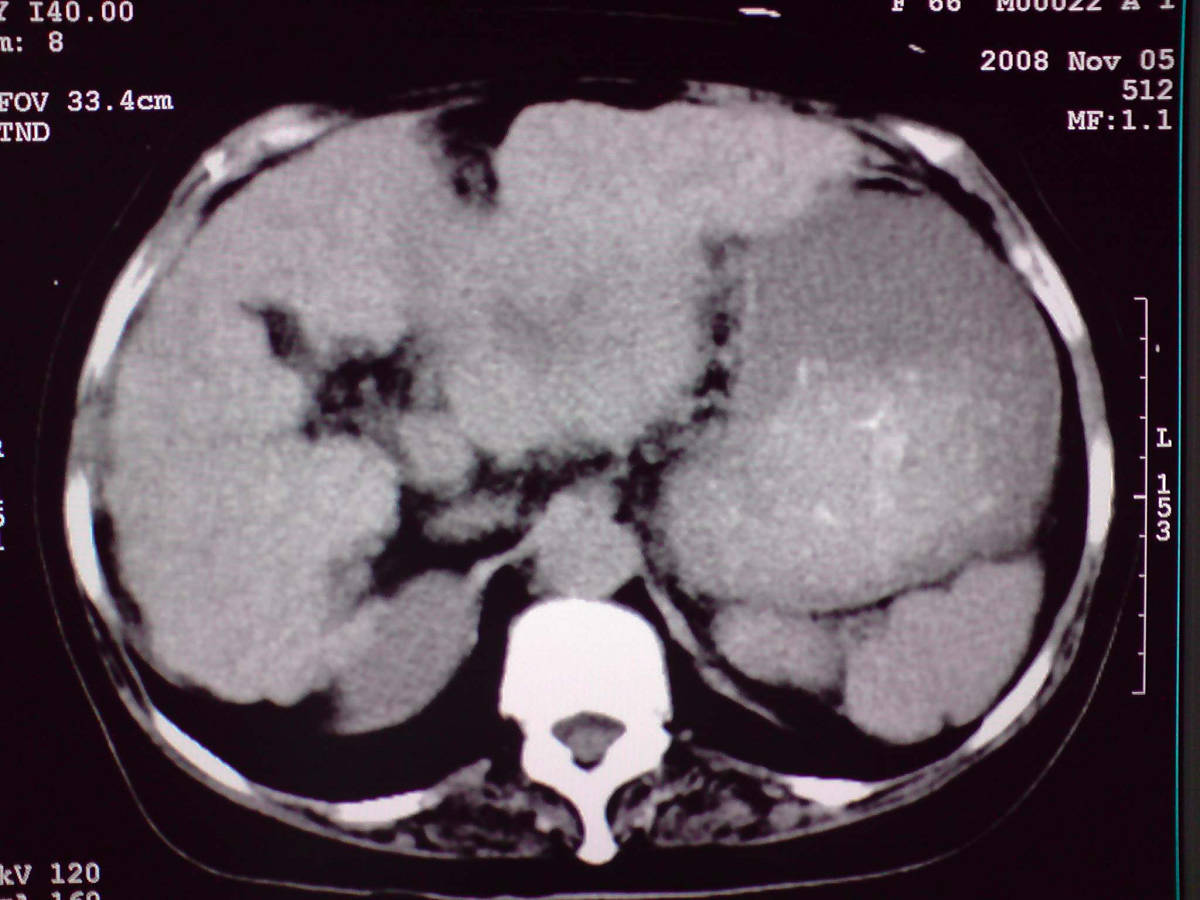

女性,60岁,上腹不适、自感胃部疼痛

小网膜区见类圆形软组织密度肿块,密度不均,内见不规则低密度区,与肝左叶分界模糊,肝脏体积缩小,密度不均匀,边缘呈波浪状,尾状叶明显增大,脾脏下缘明显超出肝脏下缘。

意见:肝硬化并外生性肝癌,建议增强扫描。

有肝硬化背景,肝胃间隙见不规则形,且密度不均匀的占位性病变,与肝左叶分界不清,首先考虑外生性肝癌可能性大,不排外肝胃间隙恶性占位肝脏受侵可能性。左肺下叶结节影,其内见空泡征,边缘见毛刺,从一元化的角度首先考虑转移。

1 肝脏各叶比例失调,形态失常,外缘呈波浪状。右叶萎缩,左叶 尾叶增大。2 腹腔内软组织密度肿块,低于肝实质密度,内见低密度区,并与肝脏界限欠清。腹膜后见肿大淋巴结,并与腹腔肿块关系密切。3 左肺下叶肿块,见边缘毛刺征及胸膜凹陷征,并与近肺门侧见异常血管相连。

综合考虑:左下肺周围性肺癌伴腹腔 腹膜后淋巴结转移!另:肝硬化!

肝脏比例失调,形态失常,外缘呈波浪状,腹腔内

小网膜区肿块内见低密度区并与肝脏界限欠清

左肺下叶偏心软组织肿块,边缘毛刺征,胸膜凹陷征,血管集束症

考虑恶性间质瘤,左肺下叶占位,肝硬化

一元论:肝硬化、外生性肝癌并左肺转移;但不除外左肺周围型肺癌可能。

感谢大家的讨论,今天拿到病理结果是肝细胞癌